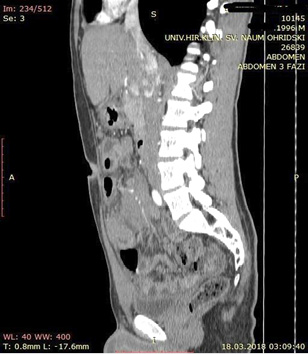

A contrast enhanced CT scan was indicated due to the palpable abdominal tumor and it revealed a formation that originates from the ileal mesentery involving the ileocolic artery and a part of the ileum with ileal wall thickening and partial obstruction (Figures 2, 3 and 4).